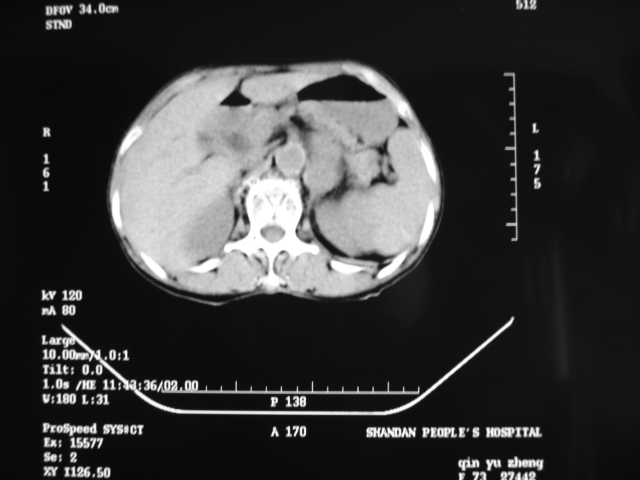

同事奶奶,73岁,腹痛一年,夜晚较重,潜血+++,拒绝增强,考虑左肾ca并腹膜后转移;请各位老师帮忙看看,谢谢!

左肾癌侵及输尿管上段,腹膜后多发淋巴结转移,脾脏钙化灶。至于潜血+++,要考虑消化道病变,本次ct片肠腔未见明显异常。

1)考虑左肾癌侵犯肾盂并腹膜后淋巴结转移。2)脾脏钙化灶。

考虑左肾癌侵犯肾盂并腹膜后淋巴结转移。